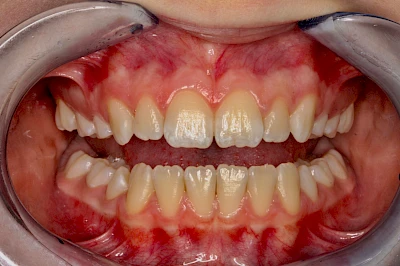

Verfärbungen an Zähnen können außen aufgelagert oder im Zahn eingelagert sein.

Äußere Verfärbungen durch Genußmittel oder Medikamente (Eisen!) lassen sich meist nur durch den Zahnarzt z. B. mit einer professionellen Zahnreinigung entfernen.

Ist ein einzelner Zahn deutlich dunkler als die Nachbarzähne kann das ein Zeichen sein, dass der Nerv abgestorben ist. Unter Umständen wurde bereits eine Wurzelkanalbehandlung vom Zahnarzt durchgeführt. Eine Abklärung durch den Zahnarzt ist in jedem Fall sinnvoll.